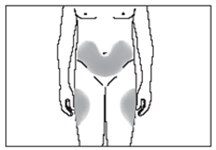

Wo sollte die Injektion bei mir erfolgen?

Die am besten geeigneten Stellen für eine Selbstinjektion sind:

·die Oberseite der Oberschenkel; und

·die Bauchdecke, mit Ausnahme des Bereichs um den Nabel herum (siehe Abbildung 7).

Wenn jemand anderes Ihnen die Spritze gibt, kann die Injektion auch auf der Rückseite der Arme erfolgen (siehe Abbildung 8).

Um zu verhindern, dass an einer Stelle Schmerzen auftreten, sollte die Injektionsstelle jeden Tag gewechselt werden.

7

8